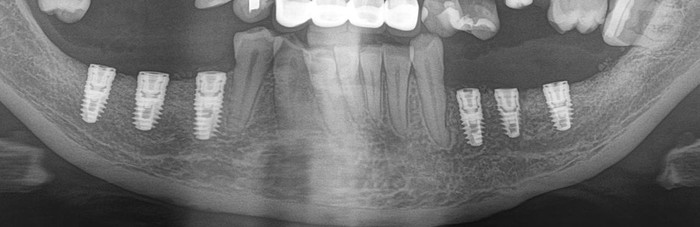

Контрольный рентгеновский снимок:

Вот так было:

А как стало на промежуточном этапе:

Согласитесь, выглядит очень даже неплохо, если опустить цвет.